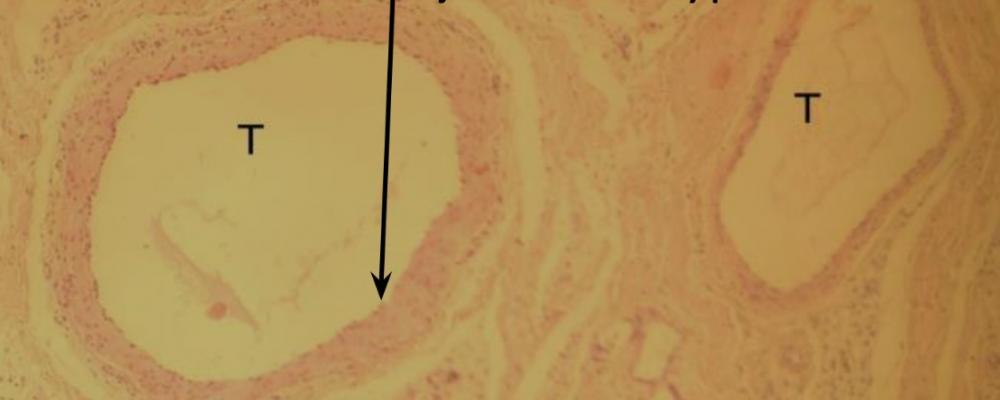

Pytanie 98

błona wewnętrzna tętnicy - nabłonek jednowarstwowy płaski (tętnica mięśniowa i żyła)

Pytanie 99

mięsień gładki okrężny (tętnica mięśniowa i żyła)

Pytanie 100

przydanka (tętnica mięśniowa i żyła)